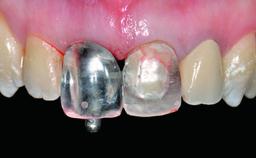

Replacement of an Ankylosed Central Incisor with a Gingival Recession: Tooth Extraction with Socket Grafting and Late Implant Placement with Simultaneous Contour Augmentation

In 2008, a healthy 15-year-old female, non-smoking patient presented at our clinic with a major esthetic problem of tooth 21. Her dental history revealed that the tooth had been avulsed by trauma years before. As a result, the replanted and temporarily splinted tooth had ankylosed and was in severe apical malposition. The ankylosed tooth exhibited a significant gingival recession that disturbed the patient greatly. Due to the patient’s low age and with her skeletal growth not completed, periodic follow-up visits were scheduled to monitor the situation until the patient was old enough for implant therapy.

Provisional Implant-Supported Prosthesis Prosthodontic margin > 3 mm apical to mucosal margin Prosthodontic margin > 3 mm apical to mucosal margin